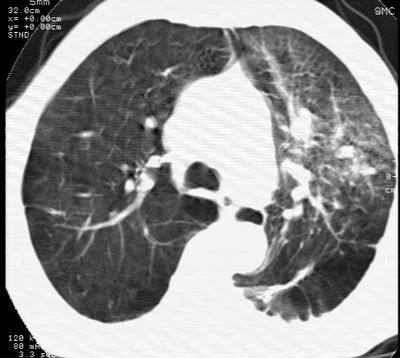

标题: CT24000:M65,胸痛,胸闷月余,既往慢支,肺气肿,肺心病 [打印本页]

标题: CT24000:M65,胸痛,胸闷月余,既往慢支,肺气肿,肺心病

1左侧胸腔积液

2左肺门站位

3双肺条索影

4右肺上叶密度增高影考虑右肺上叶肺不张,阻塞性肺炎

5纵隔内见肿大淋巴结影

左肺门肿块,相应支气管闭塞,左肺上叶、舌叶大片及散在高密度影,部分呈不张改变,两肺纹粗乱,左侧胸腔积液。考虑左侧中央型肺癌伴阻塞性改变。

左肺门见巨大软组织肿块影,直径约--,境界清,左上肺叶支气管变窄,左上肺舌叶见大片状密实影,余肺纹理增多、紊乱、纤细、部分网格状,两肺透亮度增高,纵隔内见增大多发淋巴结影,心影略左偏,左侧少量胸腔积液。